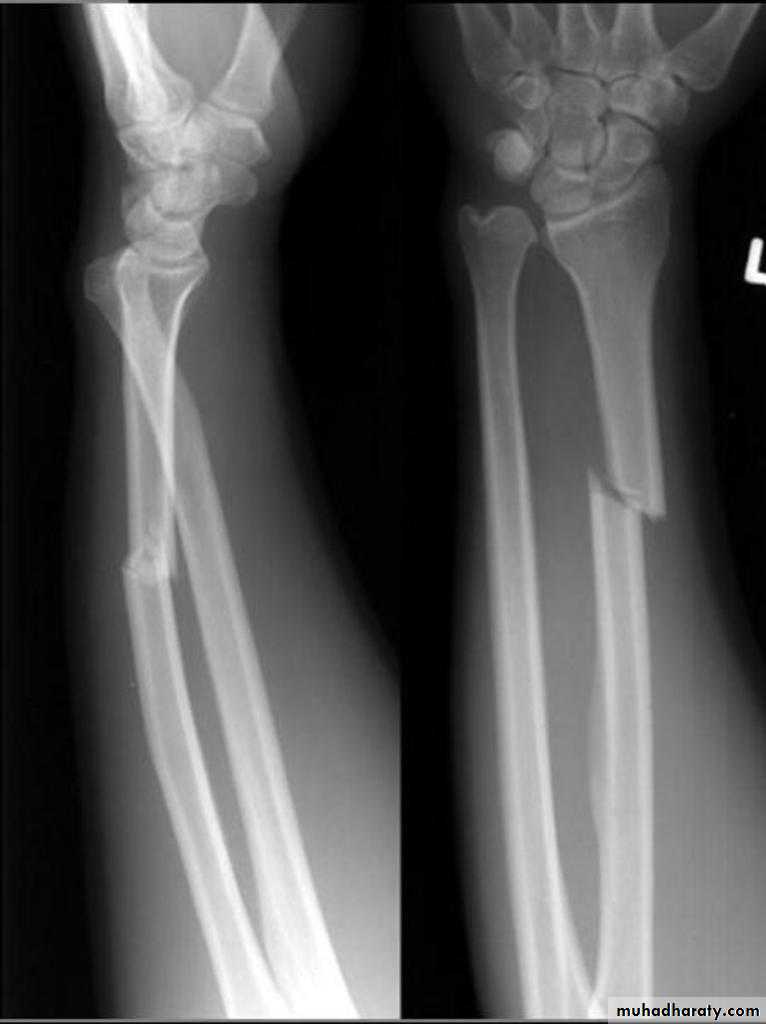

Upper limb

Fall on out stretched hand

Late complication

Rest and physiotherapy

Management

Surgery

Hand deformity